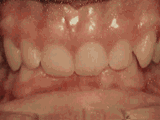

Crowded teeth, certain teeth in abnormal positions, and narrow dental arch result in localized tooth overlap. After extracting one tooth on each side and undergoing orthodontic treatment, the result can be as follows: